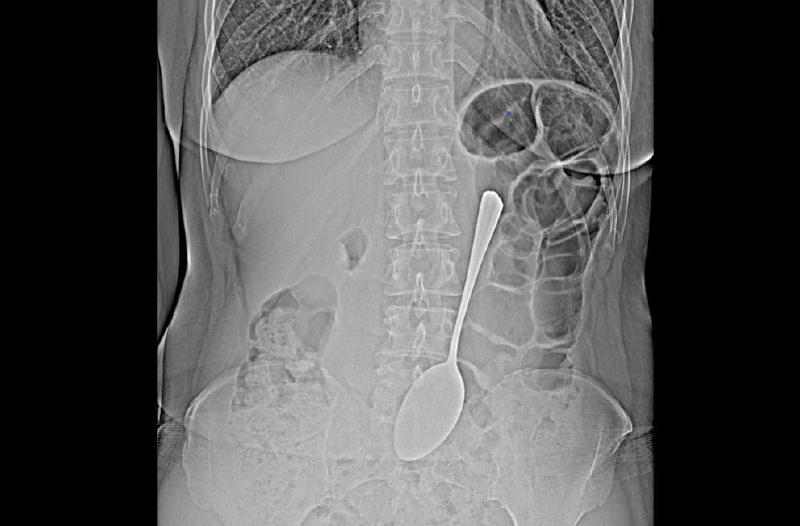

В Улан-Удэ врачи спасли женщину, проглотившую ложку.

Столовый прибор достали из желудка пациентки с помощью эндоскопа и соответствующих инструментов. Это позволило избежать сложной хирургической операции.

— Инородные предметы в желудке могут спровоцировать перфорацию желудка, кишечную непроходимость. Если мелкие предметы вроде монет могут выйти из организма самостоятельно, то в случае со столовой ложкой всё могло быть серьезнее, — комментирует врач-эндоскопист БСМП Бабудоржиева Валентина.

После операции женщину отпустили домой. Почему и как она проглотила ложку — пациентка не объяснила.